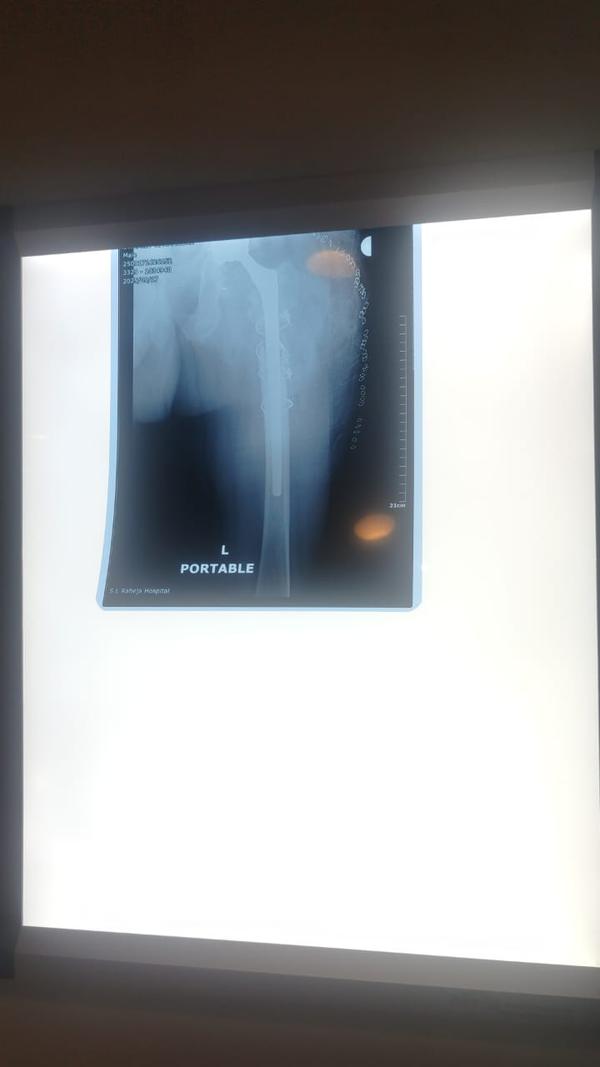

Revision Hip And Knee Replacement

Dr Randive has 25 years experience in Revision Knee and Revison Hip Replacement surgeries. It took him more than 25 years of training hard work and thousands of surgeries to achieve excellence in Revision Knee and Hip Surgeries. He has successfully achieved this milestone through extensive training.